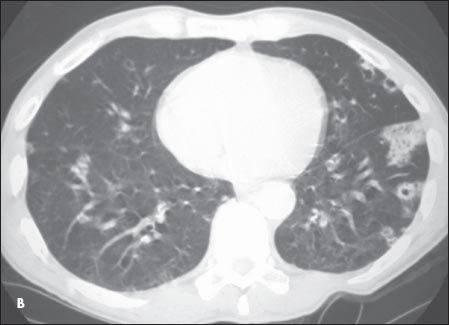

A CT scan of the chest showed subpleural cavitating lung nodules (A and B). Blood cultures grew Staphylococcus aureus, and an echocardiogram confirmed the diagnosis of infective endocarditis.

Septic pulmonary embolism is an uncommon disorder that generally presents with an insidious onset; characteristic features include fever and lung infiltrates associated with an active focus of extrapulmonary infection.1,2 Risk factors are injection drug use, indwelling catheters/ devices, pelvic thrombophlebitis, and suppurative processes in the head and neck.3,4 The embolic blood clot that leads to an infarction and the microorganisms contained in the clot incite a focal abscess.4

The triad of bacteremia, fever, and multiple cavitary pulmonary infiltrates on a chest radiograph should always prompt a search for right-sided infective endocarditis.2,3